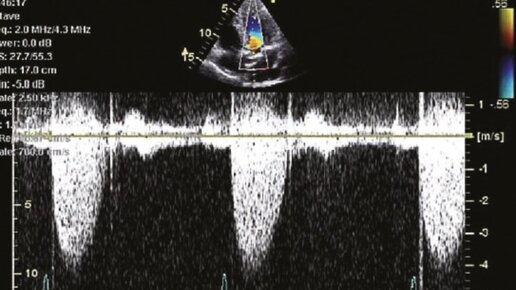

Как сегодня бьётся ваше сердце? По общему признанию, большинство людей, вероятно, не знают этого ответа. Но знание и эффективное управление фракцией выброса может оказать большое влияние на качество вашей жизни и здоровья. Отслеживание этого не только поможет вашему врачу лечить вас более эффективно, но и приведет к лучшим результатам. Низкая фракция выброса прямо пропорциональна выживаемости. Улучшая его, вы улучшаете свои перспективы выживания. Что такое фракция выброса? Сердце имеет две основные мышечные камеры: левый и правый желудочек...